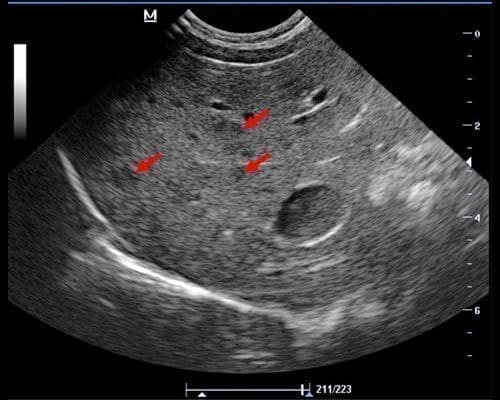

Ultrasonography of the Liver Part 1 >>

Ultrasonography of the Liver Part 2 >>

Ultrasonography of the Liver Part 3 >>